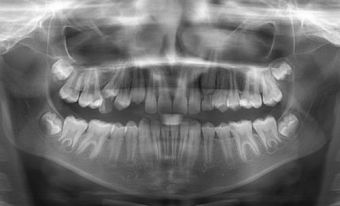

Fig 2- Radiografie panoramica a unui adult; se observa toti dintii prezenti, edentatii, sinusurile maxilare, oasele maxilar si mandibular, articulatiile temporo-mandibulare, fosele nazale, traseul canalului alveolar inferior. Este o un mod de orientare foarte bun pentru crearea unui plan de tratament.